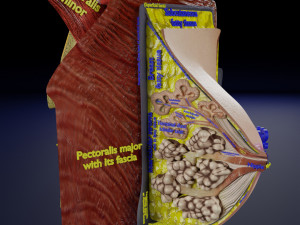

A blend model of brain along with its covering layers (meninges), skull bone and scalp labelled in detail and anatomically precise. The parts depicted are white, gray, pia, arachnoid, dura, bone, skin, fat, aponeurosis, periosteum, falx cerebri and more.